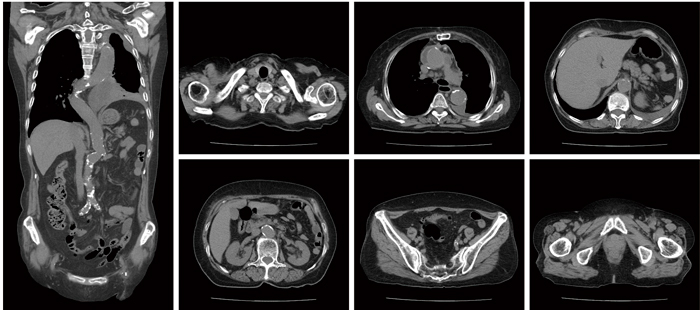

また,SCENARIAでは,独自の三次元画像再構成アルゴリズム“CORE法”を採用している。CORE法は,画素ごとに再構成で使用する収集データ範囲を最適化するアルゴリズムである。実効的なコーン角を狭くすることができるため,コーン角に起因するアーチファクトを低減することが可能になる。また,実効コーン角が小さいことで,高速ピッチを利用することができることも利点である。0.35s/rotと高速ピッチを組み合わせることで,最大180mm/sの撮影スピードを実現した(図6)。

図6 180mm/s(0.35s/rot, BP=1.58)で700mmを3.8sで撮影